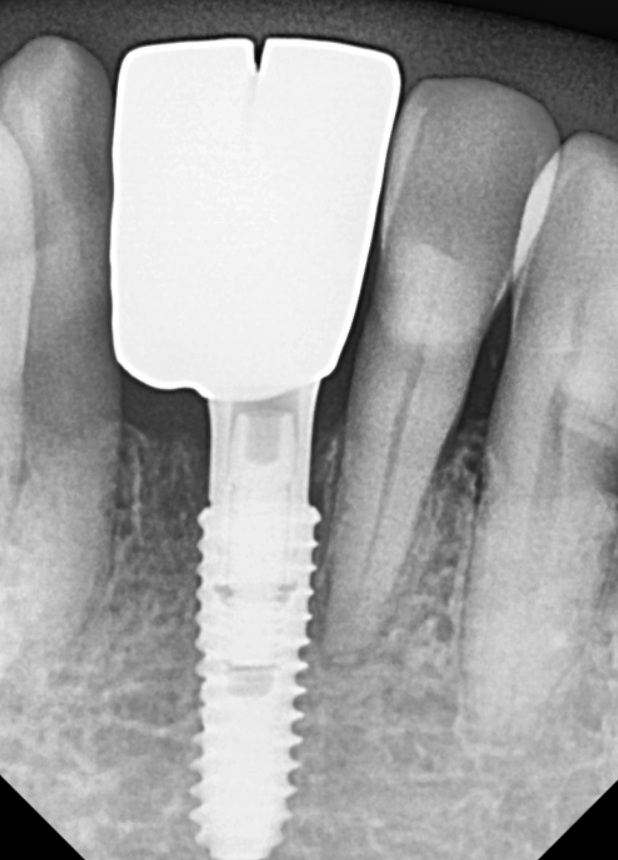

식립 3개월 뒤,

뼈와 임플란트가 단단히 굳은 것을 확인하고

디지털 구강스캐너로 본을 떴습니다.

최종 완성된 모습입니다.

뿌리는 1개지만,

보철물은 2개가 들어갔습니다.